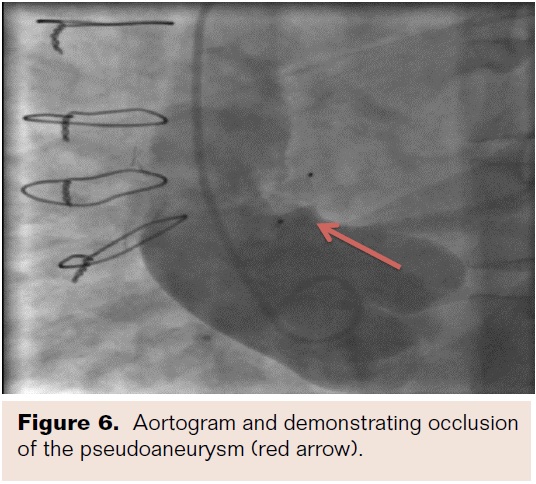

The glidewire was removed and a 6 mm Amplatzer Vascular Plug 4 (VP4; St. Jude Medical) was advanced through the DAC catheter and half of the device was exposed in the PSA. The device was pulled back so that the second dome was exposed on the aortic side (Figure 5). Aortography was performed to demonstrate occlusion and the device was assessed for stability. Once stability and closure were confirmed, the device was released. Repeat aortography revealed no residual leak (Figure 6). There were no complications of the procedure and the patient did well post-procedure. This patient received standard post aortic dissection follow-up with CT angiogram at discharge, CT angiogram 1 month after discharge, and then subsequent yearly CT angiograms. No subsequent bloodwork was performed.